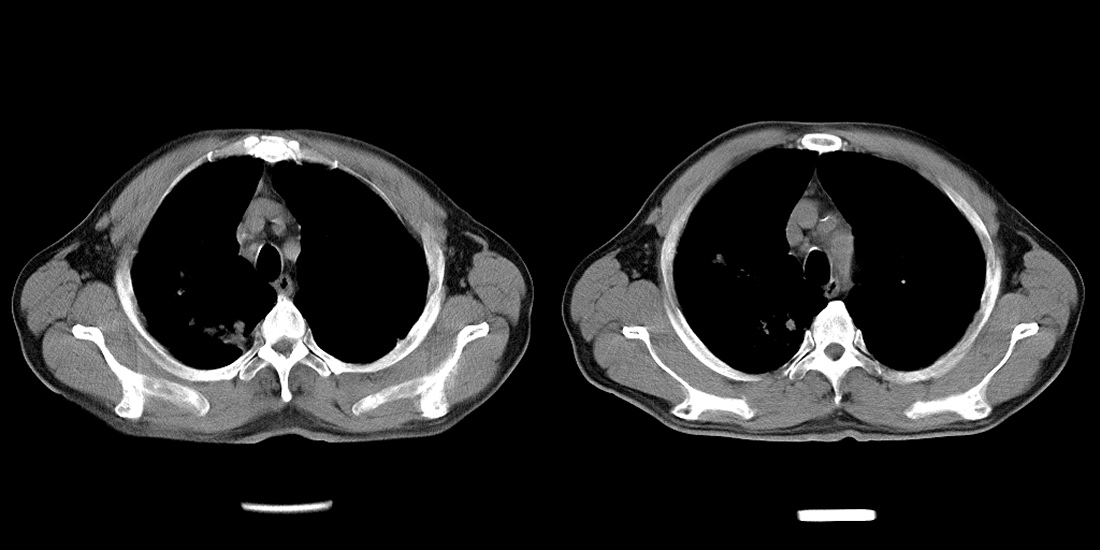

标题: CT10251:男性56岁,结核球? [打印本页]

标题: CT10251:男性56岁,结核球?

56岁男性,低热、消瘦,曾x线诊断肺结核。

两肺结核,左肺结核球。

双肺结核伴左上肺结核球形成

两肺多形性病变,支持肺结核.

两肺多形性病变,且在结核好发部位。支持肺结核.